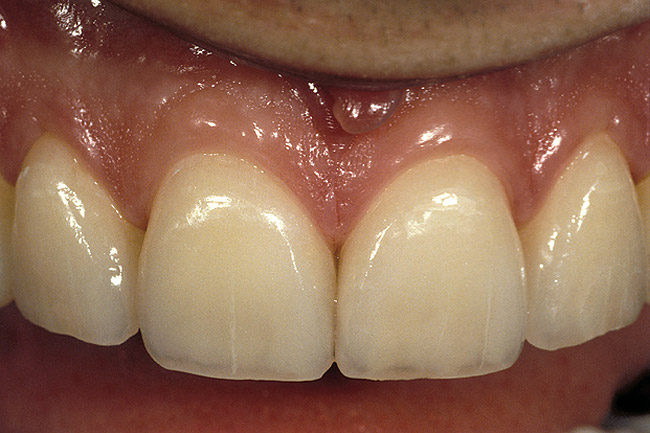

Figure 2  Note the invisibility of the marginal line in the completed veneers, even though the margin has not been carried below tissue.

Figure 2